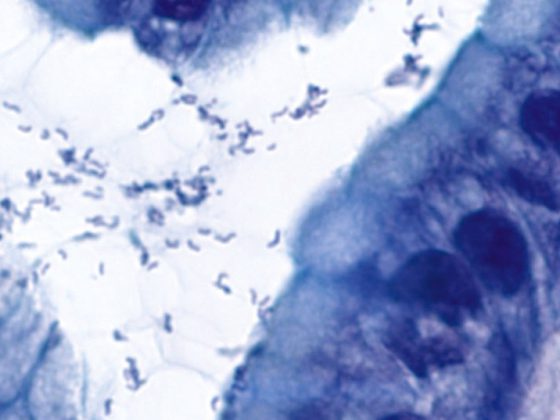

helicobacter2

Magenlymphom vom MALT-Typ